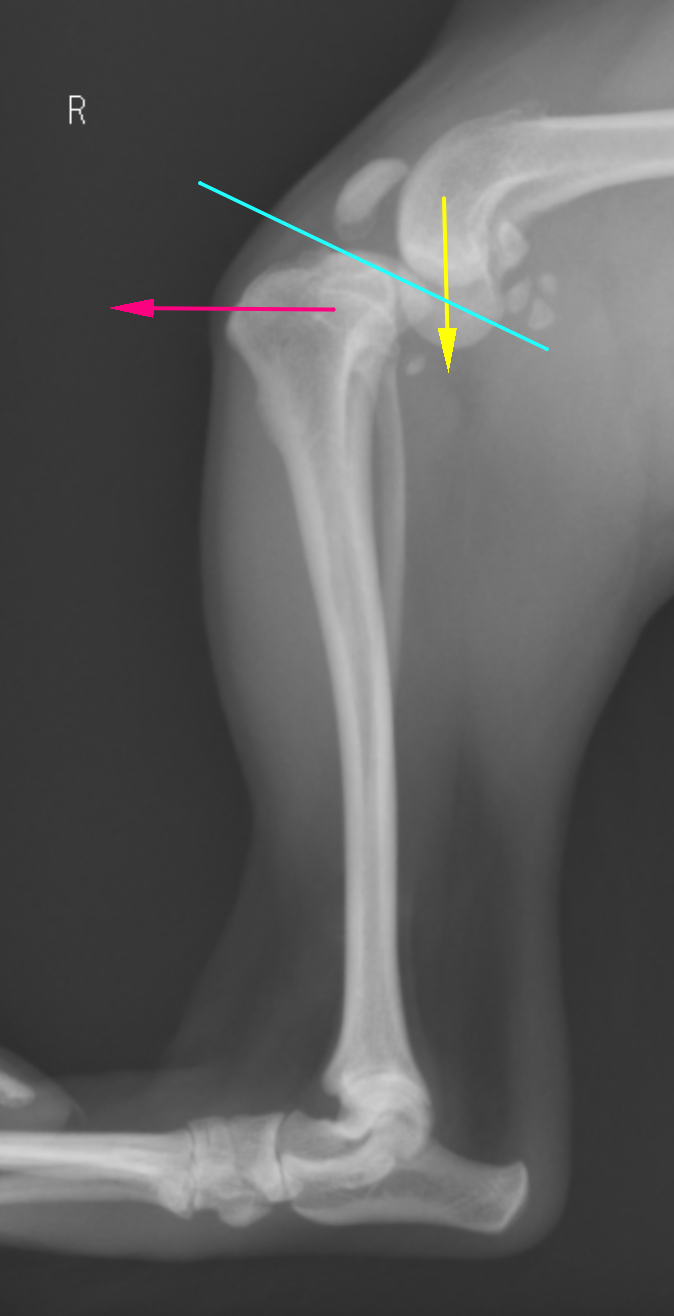

TPLOは脛骨高平部という部分を水平にする術式ですが、その優れた点として、骨を円形に切断することで、関節の回転中心を変化させない、骨に伝わる重心を変化させないというものが挙げられます。前十字靭帯が切れてしまうとTPAという脛骨高平部の角度があるが故に脛骨が前方に進んでいこうとします。これを脛骨前方運動=CrTTと言います。斜めの椅子に腰掛けると椅子が後ろにすすむのをイメージするとわかりやすいかと思います。TPAを水平にすることで、前十字靭帯が断裂していてもCrTTが生まれない足にしてしまうというのがTPLOになります。

治療には特殊なTPLOソーという丸い鋸で骨を切断して回転させ、TPAを5度に近づけることでCrTTをなくすTPLO法というものを行います。これにより、前十字靭帯がなくても歩行可能となります。最小で1kg代の子から、大きい子だと70kg代の子まで対応が可能です。